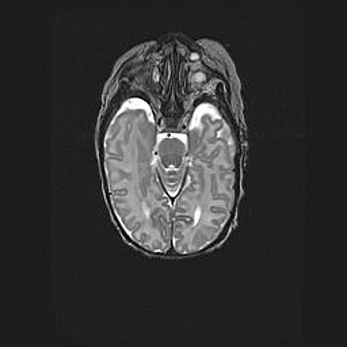

Лейкомаляция с кистозно-глиозной дегенерацией головного мозга.

Возраст: 2 месяца 25 дней

Вес: 6400 г

Окружность головы: 40 см

Срок гестации: 41 неделя

Лейкомаляцию относят к ишемически-гипоксическим повреждениям головного мозга, диагностируемым у новорожденных. При лейкомаляции в головном мозге обнаруживают очаги некроза, возникшие после тяжелой гипоксии и нарушения кровотока. В процессе морфогенеза очаги проходят три стадии: 1) развития некроза, 2) резорбции и 3) формирования глиозного рубца или кисты. Перивентрикулярная лейкомаляция (ПЛ) встречается примерно в 12% случаев среди новорожденных, обычно – у недоношенных детей, причем, частота ее зависит от массы, с которой младенец появился на свет. Наибольшее число малышей страдает лейкомаляцией, если масса при рождении 1500-2500 г.